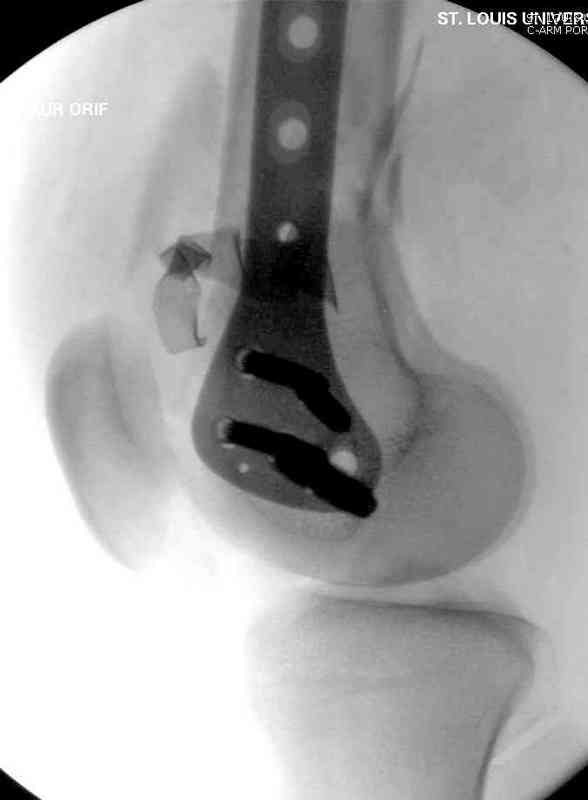

Латерально пластину защитили ушиванием

илио-тибиального тракта, а медиальная сторона была ушита мышцей, и все раны закрыли ваккумированием (VAC)

На третий день после Irrigation & Debridment закрыли все раны за исключением компартментальной раны из-за отека, медиально в дефект кости установили Putty Grafton Bone Substitute. На компартментальную рану вакуум и мероприятия по сближению краев раны резиновой стяжкой.

На 9й день с момента травмы ушили рану без натяжения. Больной получает реабилитацию, движения коленного сустава с помощи CPM-continuous passive motion machine. Сегодня выписан.